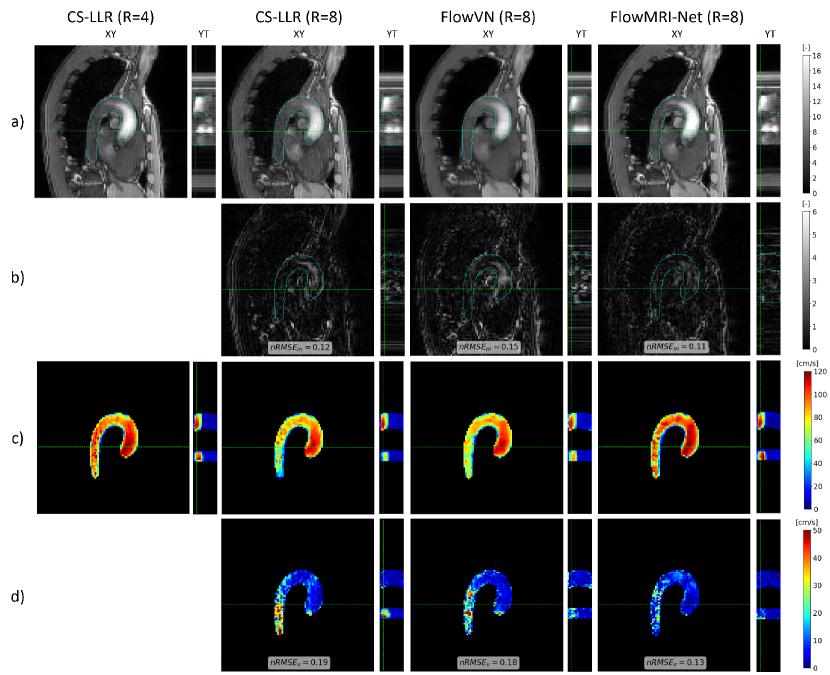

The quantitative metrics for aortic reconstructions using CS-LLR, FlowVN, and FlowMRI-Net are summarized in Table 2, with the image magnitudes, velocity magnitudes, and their errors of an exemplary healthy volunteer shown in Fig. 2 and 3 for 8-fold and 16-fold prospective undersampling, respectively. Visual image magnitude quality and values are similar for CS-LLR and FlowMRI-Net reconstructions for both undersampling factors, whereas FlowVN shows increased spatial and temporal blurring in the image magnitudes. Velocity magnitudes during peak systole are generally underestimated by CS-LLR and FlowVN, particularly in the descending aorta where SNR is lower due to the higher distance to the coils. This underestimation of velocity magnitude is reflected by the inferior and values of CS-LLR and FlowVN compared to FlowMRI-Net for both undersampling factors.

The superior reconstruction quality of prospectively undersampled aortic 4D flow MRI for R = 8 and 16 was demonstrated both qualitatively (Fig. 2 and 3) and quantitatively (Table 2), with FlowMRI-Net recovering more accurate structural details and hemodynamic features in the image magnitudes and velocity magnitudes compared to CS-LLR and FlowVN reconstructions, resulting in lower and values. Compared to the fully sampled 2D breath-hold scans, FlowMRI-Net accurately captures peak velocity in FH direction, as opposed to CS-LLR and FlowVN, which both underestimate peak velocity (Fig. 4). Velocities in RL and AP direction remain noisy, which can be explained by the relatively high venc = 150 cm/s compared to the maximum velocities that occur in those two directions for non-pathological flow (vmax ¡ 50 cm/s). The spatiotemporal blurring of FlowVN reconstructions in the work was not observed in the original paper [18], which may be explained by the change in training data and the switch from retrospectively-undersampled data with additional noise as input to prospectively-undersampled data. Also note that in the original paper the CS-LLR was not GPU-accelerated, hence the reported 30-fold increase in reconstruction speed, which does not hold anymore in this work as CS-LLR was also run on a GPU.